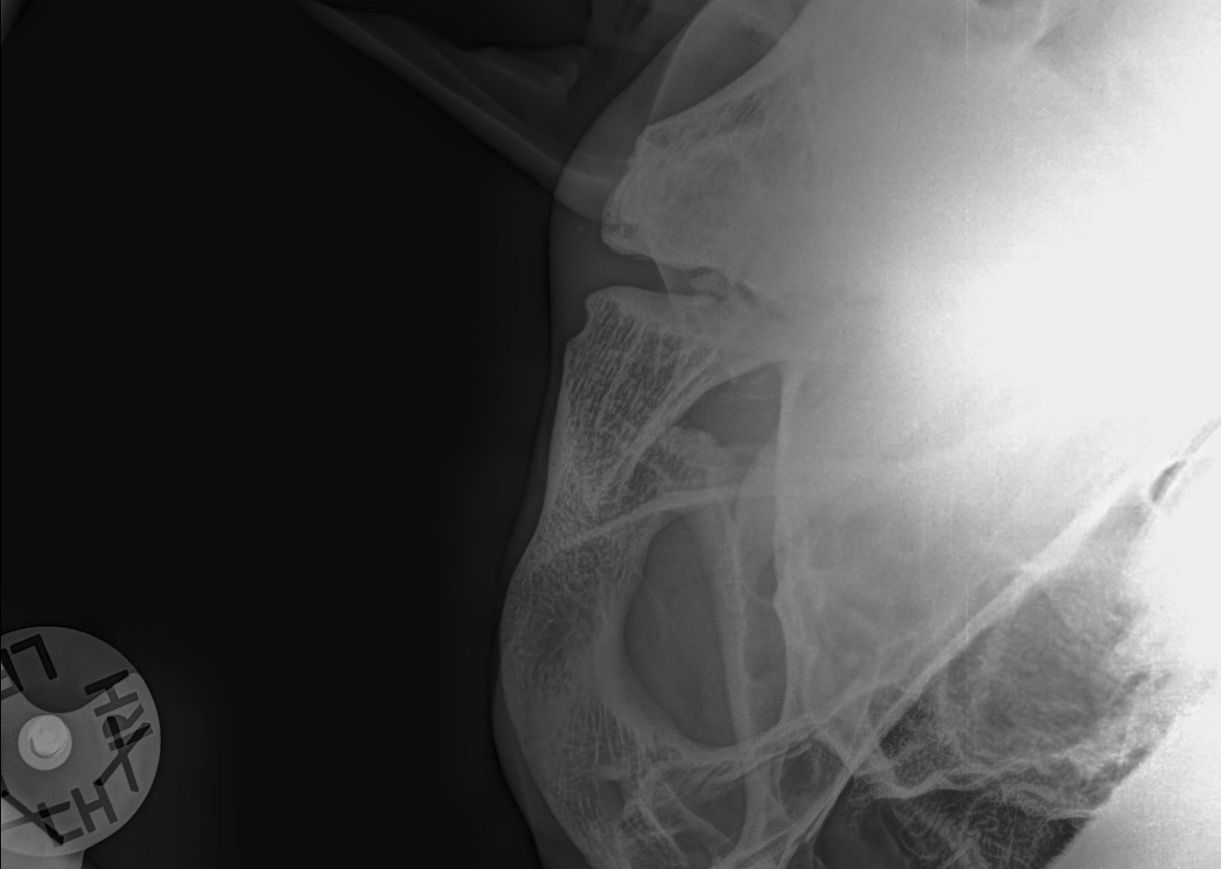

Weiterführende Untersuchungen: Röntgen

- makroskopische Umfangsvermehrung am linken Kiefergelenk

- röntgenologische Untersuchung beider Kiefergelenke zum Seitenvergleich

- beidseitige Befunde

Diagnose: beidseitige Kiefergelenksarthrose